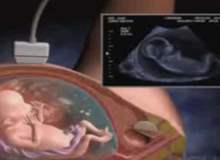

Klinik olarak, hamileliğin 2. haftası, kadının henüz hamile olmadığı bir dönemi kapsar. Kadın hamile olmamakla birlikte sağ veya sol yumurtalığında, döllenmeyi başlatacak olan yumurtanın olgunlaşması devam etmektedir.